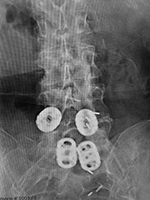

Interbody vertebral cages |

The cages are at L1-2 with bilateral pedicle screws and rods going from L1 to L3 for degenerative lumbar spine disease. |